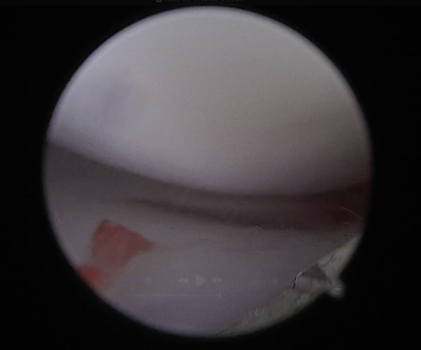

.png)

전방 십자인대 손상 확인 된 모습

후방 십자인대 부분 손상 및 염증성 변화 확인

손상되지 않은 반월판 확인 된 모습